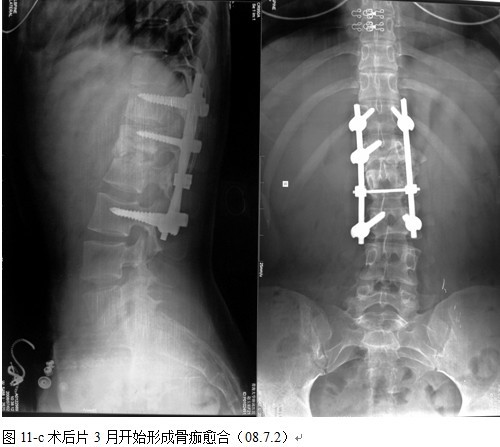

本组手术用时间3~4h , 平均3.5h 。术中出血300~500ml , 平均约350ml 。术后症状完全缓解,无神经功能障碍加重等并发症,1例营养差的老年患者伤口出现窦道,1例因肝功能差,术后未口服抗痨药,伤口出现窦道,经换药后二期愈合,其余病例伤口均一期愈合。马尾神经受损的患者术后基本恢复正常。术后一周后凸角平均 5.4°后凸畸形平均矫正90%以上, 最终后凸角平均8.3°,后凸角度平均丢失4.2°。随访3个月有87%(40/46)有骨痂形成,6个月91.3%(42/46)明显骨性愈合(见图),其余4例9-12个月内愈合,随访时间3-32个月,平均11个月,46例患者中2例在术后2个月和3个月时背部形成脓肿,换药后治愈。2例出院1月后并发结核性脑膜炎,治疗后好转。1例因椎弓根钉偏外,刺激神经根,5个月后从侧方脱出,疼痛加重,因前后路植骨完全愈合,取出后症状完全缓解。

术后卧床2 周后,配戴支具下床活动。支具配戴时间3~4 个月,术后继续四联抗痨药物治疗,吡嗪酰胺应用3 个月后停药,3个月定期复查肝功,血沉,C-反应蛋白及X线片,同时口服保肝药物 ,持续治疗9~12个月。